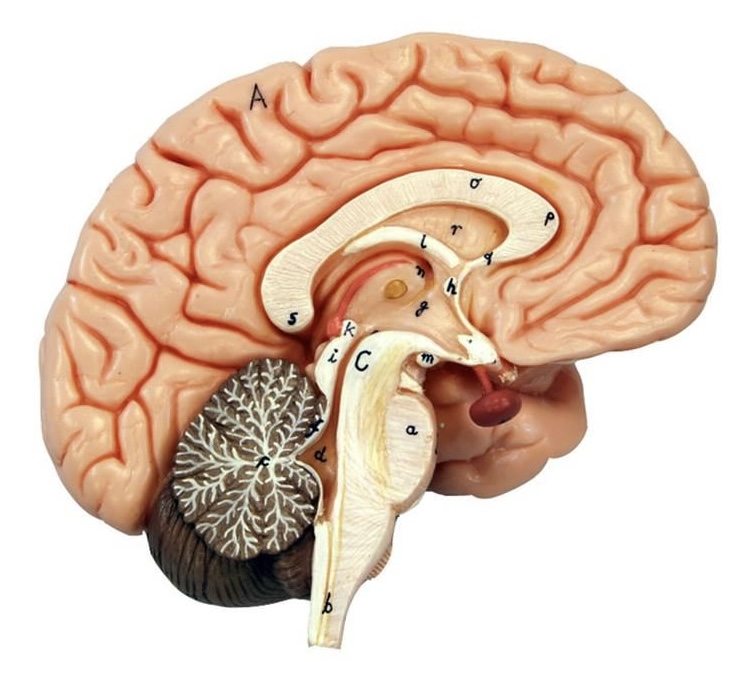

What is D?

lateral ventricle

Imagine thin membrane separating the 2 lateral ventricles

septum pellucidum

What is C?

3rd ventricle

What is B?

cerebral aqueduct

What is A?

4th ventricle

What is below A at the very end?

central canal (spinal cord)

What is C?

midbrain

tectum (corpora quadrigemina): superior colliculus

tectum (corpora quadrigemina): inferior colliculus

What is a?

pons

medulla oblongata

intermediate mass of thalamus

hypothalamus

What is the pink bulb?

pineal gland

corpus callosum

fornix

What is A?

cerebral cortex

cerebral tracts

cerebral hemispheres

longitudinal fissure

What are these ridges?

gyri

What are these shallow grooves?

sulci

Divides parietal from frontal lobe

central sulcus

precentral gyrus

postcentral gyrus